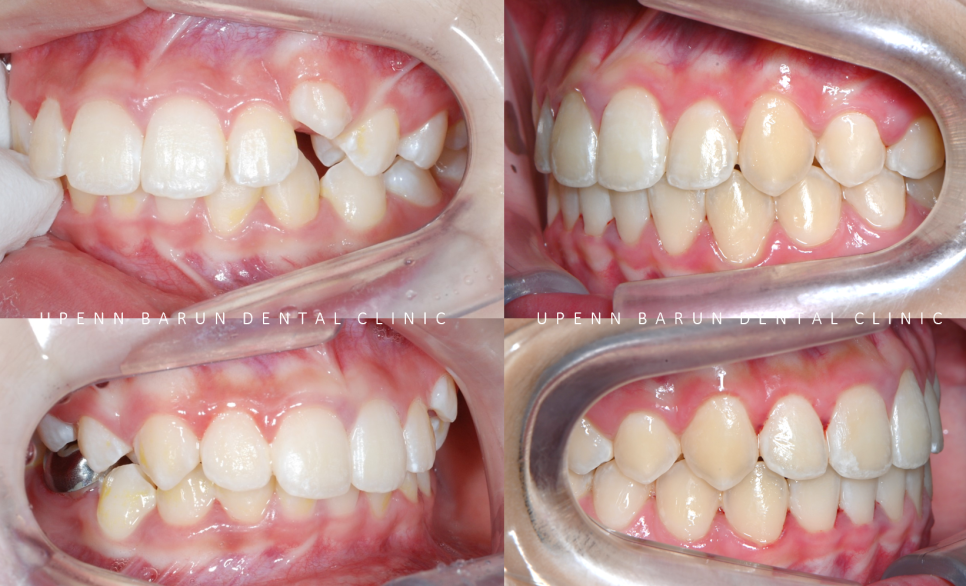

인비절라인 치료기간 22.01 ~ 24.06

세번째 클린체크를 마친 후 사진입니다

wow~!

치아 배열부터 교합까지

거의 완벽하게 마무리가 된것처럼 보이지만

꼼꼼한 닥터킴의 열정은 끝나지 않았는데요 ><

교정기간: 22/1~24/6

치열이 고르지 않고

송곳니가 도드라져 보였던 이전과는 달리,

청소년기인비절라인 교정 후

정중선이 맞아지고 치열이 가지런해지면서

보다 자연스러운 미소를 지어주었습니다.